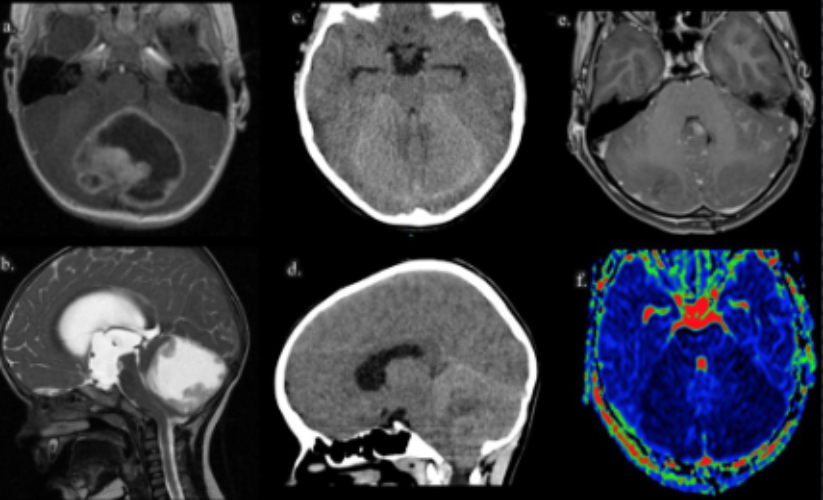

Diagnostic modalities covered in the training program include x-ray, ultrasound, computed tomography (CT), CT angiography, magnetic resonance imaging (MRI), MR angiography, fetal MRI, diffusion tensor imaging (DTI), functional MRI (fMRI), MR spectroscopy (MRS), and other advanced imaging techniques including CT and MR perfusion. Neuroendovascular procedures are performed in two state-of-the-art biplane angiography suites. Fellows have the elective opportunities to rotate in our active neuroendovascular surgery service with rotations also available in neurovascular ultrasound, anesthesiology pain management, and neuropathology.